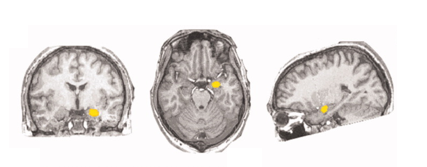

原来,尼古丁成瘾有一个核心特征——吸烟线索反应(smoking cue reactivity),即对与吸烟相关的提示表现出显著的生理和主观反应。在这个过程中,吸烟成瘾者大脑中的杏仁核会消耗更多氧气和营养物质,引起循环系统发送更多高氧血液,从而导致激活区域的血氧水平增加。吸烟线索反应可能是复吸发作的重要诱发因素,也可能从根本上影响着戒烟者的控制能力。

大脑中不同位置的杏仁核|参考文献[8]

[8] Zhang X,Chen X,Yu Y,et al. Masked smoking-related images modulate brain activity in smokers[J]. Human Brain Mapping,2009,30 (3):896–907.